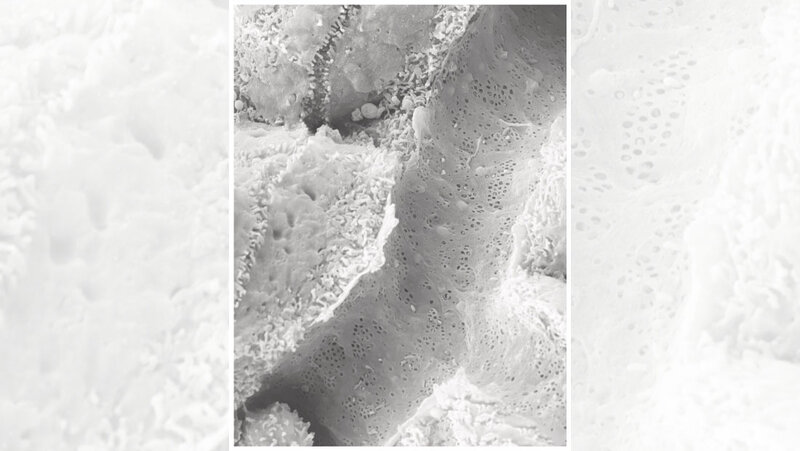

Sydney Balkenhol vom Institut für Stoffwechselphysiologie der HHU und vom DDZ, Erstautorin der Studie, weist auf eine Entdeckung des Teams hin, die mithilfe der Rasterelektronenmikroskopie gemacht wurde: „Auch in einem speziellen Mausmodell für Fettleber und Typ-2 Diabetes mellitus waren die ‚Fenster‘ in den kleinsten Blutgefäßen der Leber verschlossen.“ Dr. Daniel Eberhard, der weitere Erstautor, ergänzt: „Wir konnten den Effekt auch umkehren. Indem wir das Signalmolekül hemmten, konnten wir die Leber entfetten und so ihre Funktion wieder verbessern.“ Der Korrespondenzautor Prof. Dr. Eckhard Lammert, Leiter des Instituts für Stoffwechselphysiologie an der HHU und des Instituts für Vaskular- und Inselzellbiologie am DDZ, erhofft sich aus den Entdeckungen langfristig einen therapeutischen Ansatz auch für den Menschen: „Möglicherweise kann das von uns identifizierte Signalmolekül SEMA3A genutzt werden, um die MASLD und ihre Folgen frühzeitig zu verhindern. Doch müssen wir zunächst die Prozesse auch beim Menschen näher untersuchen.“